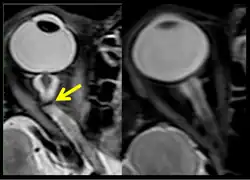

The third case of visual changes while on board the ISS had no changes in visual acuity and no complaints of headaches, transient visual obscurations, diplopia or pulsatile tinnitus during the mission. Upon return to Earth, no eye issues were reported by the astronaut at landing. Fundus examination revealed bilateral, asymmetrical disc edema. There was no evidence of choroidal folds or cotton-wool spots, but a small hemorrhage was observed below the optic dics in the right eye. This astronaut had the most pronounced optic-disc edema of all astronauts reported to date, but had no choroidal folds, globe flattening or hyperopic shift. At 10 days post landing, an MRI of the brain and eyes was normal, but there appeared to be a mild increase in CSF signal around the right optic nerve.[5]